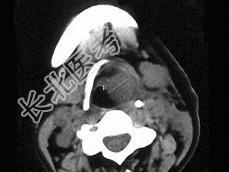

- 单项选择题女,54岁, 鼻咽部异物感约3个月,PE: 左侧声带固定,可见肿物, CT如图所示,应诊断为 ( )

B、喉癌